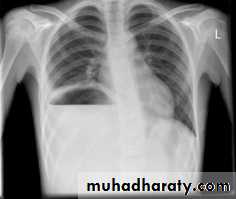

Large hiatus hernia, seen with fluid in stomach

Right Pericardial fat pad

Rt. Cardiophrenic pericardial cyst

Morgagni, retrosternal, diaphragmatic hernia